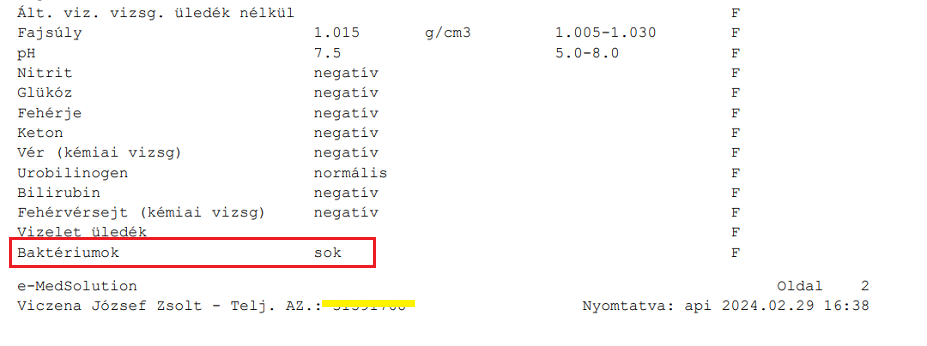

10./ Március 7. Ismét Semmelweis I.sz. Belgyógyászati és Onkológiai Klinika:

Konzultáció dr. Ledó Nóra nefrológussal, vizeletvizsgálat, mellkas röntgen. A kórházba nem vette fel Zsoltot még most sem, pedig a fiam azt ismételgette, „De én akut állapotban vagyok, tudom milyen amikor nagy baj van és amikor nincs, ez egy nagyon súlyos akut állapot!” Nem érdekelte. Pedig most már „baktériumok: zsúfolva/látótér” volt az eredmény, vagyis maximális baktériumvizelés. Úgy hogy csupán egy-két napja fejezte be az ügyeleten felírt Suprax antibiotikumot. Csoda, hogy a baktérium bejelzett, ráadásul ennyire, mert az antibiotikum teljesen „meghamisítja” a sima vizeletvizsgálatot is, ezért írnak elő 4-8 nap szünetet orvosok újabb tenyésztések előtt – van olyan antibiotikum, amelyik 15-6 nap után ürül csak ki az ember szervezetéből teljesen… (pl. azitromicin)